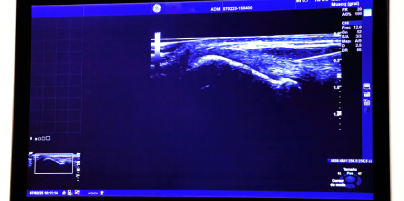

Ecografía Musculoesquelética

La ecografía es una prueba diagnóstica en la que se utiliza el ultrasonido para poder tener una imagen de los diferentes tejidos, órganos o estructuras de nuestro cuerpo.

Se valorará el motivo de consulta con una serie de test de movilidad ortopédico y palpación, que junto con la ecografía, nos ayudarán a precisar el diagnóstico.

Se hará una nueva valoración tanto física como ecográfica de la evolución de la lesión desde la última sesión, para saber si ha habido algún cambio con respecto a la situación inicial.